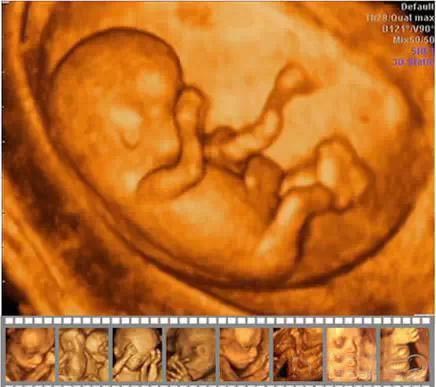

四維彩超的全稱為四維彩色超聲診斷儀,是目前世界上最先進的彩色超聲設備。其領先的科技性,檢查時能夠表面成像,能夠顯示出胎兒的實時動態(tài)活動圖像,或者其它人體內(nèi)臟器官的實時活動圖像。由于四維彩超能夠表面成像,胎兒的唇腭裂、四肢發(fā)育畸形、腦膜膨出、脊柱裂、腹壁裂等先天畸形能更清晰地查出來。四維彩超的診斷資料有利于醫(yī)生檢測出各種異常,對于胎兒的成長發(fā)育做出準確的判斷。

四維彩超胎兒畸形篩查

1.胎兒面部畸形:如唇腭裂等。

2.神經(jīng)系統(tǒng):無腦兒、腦積水、小頭畸形、脊柱裂及腦脊膜膨出。

3.消化系統(tǒng):臍部腸膨出、內(nèi)臟外翻、腸道閉鎖及巨結腸等。

4.泌尿系統(tǒng):腎積水、多囊腎及巨膀胱、尿道梗阻。

5.其它畸形:短肢畸形,聯(lián)體畸形,唇裂、四心腔。

6.對孕婦來說,也能檢查出是否存在羊水過多或過少的問題。

不過,四維彩超也不是萬能的,有些疾病,比如新生兒耳聾、白內(nèi)障等就無法檢測出來。